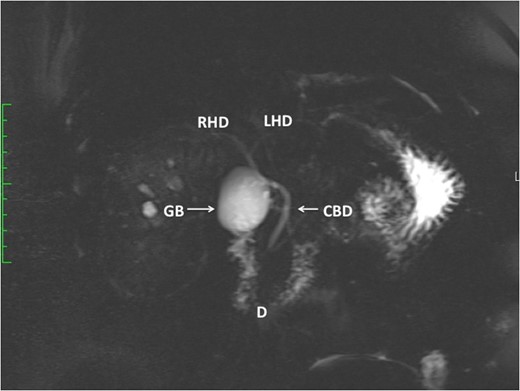

A review of hospital records confirmed elective laparoscopic cholecystectomy for biliary colic 3 years prior. The operation notes described an uncomplicated procedure with no apparent deviation from standard technique. A ‘1 × 2 × 3 cm thin-walled gallbladder with multiple stones and features of chronic cholecystitis’ was described on pathology reports. With supportive management, there was prompt resolution. The gallbladder remnant was demonstrated on MRCP (Fig. 1).

This MRCP demonstrates a large gallbladder remnant (GB). The anatomy of the duodenum (D), CBD, left (LHD) and right hepatic ducts (RHD) are normal. There are no CBD stones present.